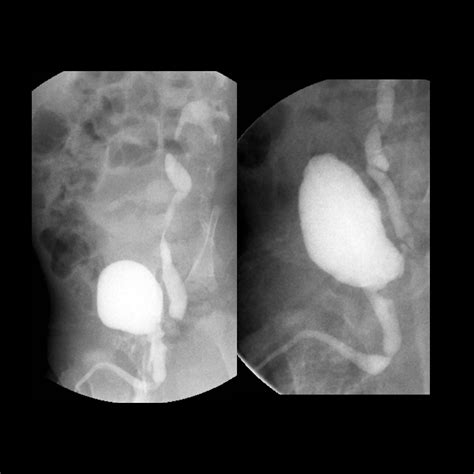

• Voiding cystourethrogram (VCUG): This test involves injecting contrast dye into the bladder and taking X-rays to visualize the urethra and detect the presence of valves.